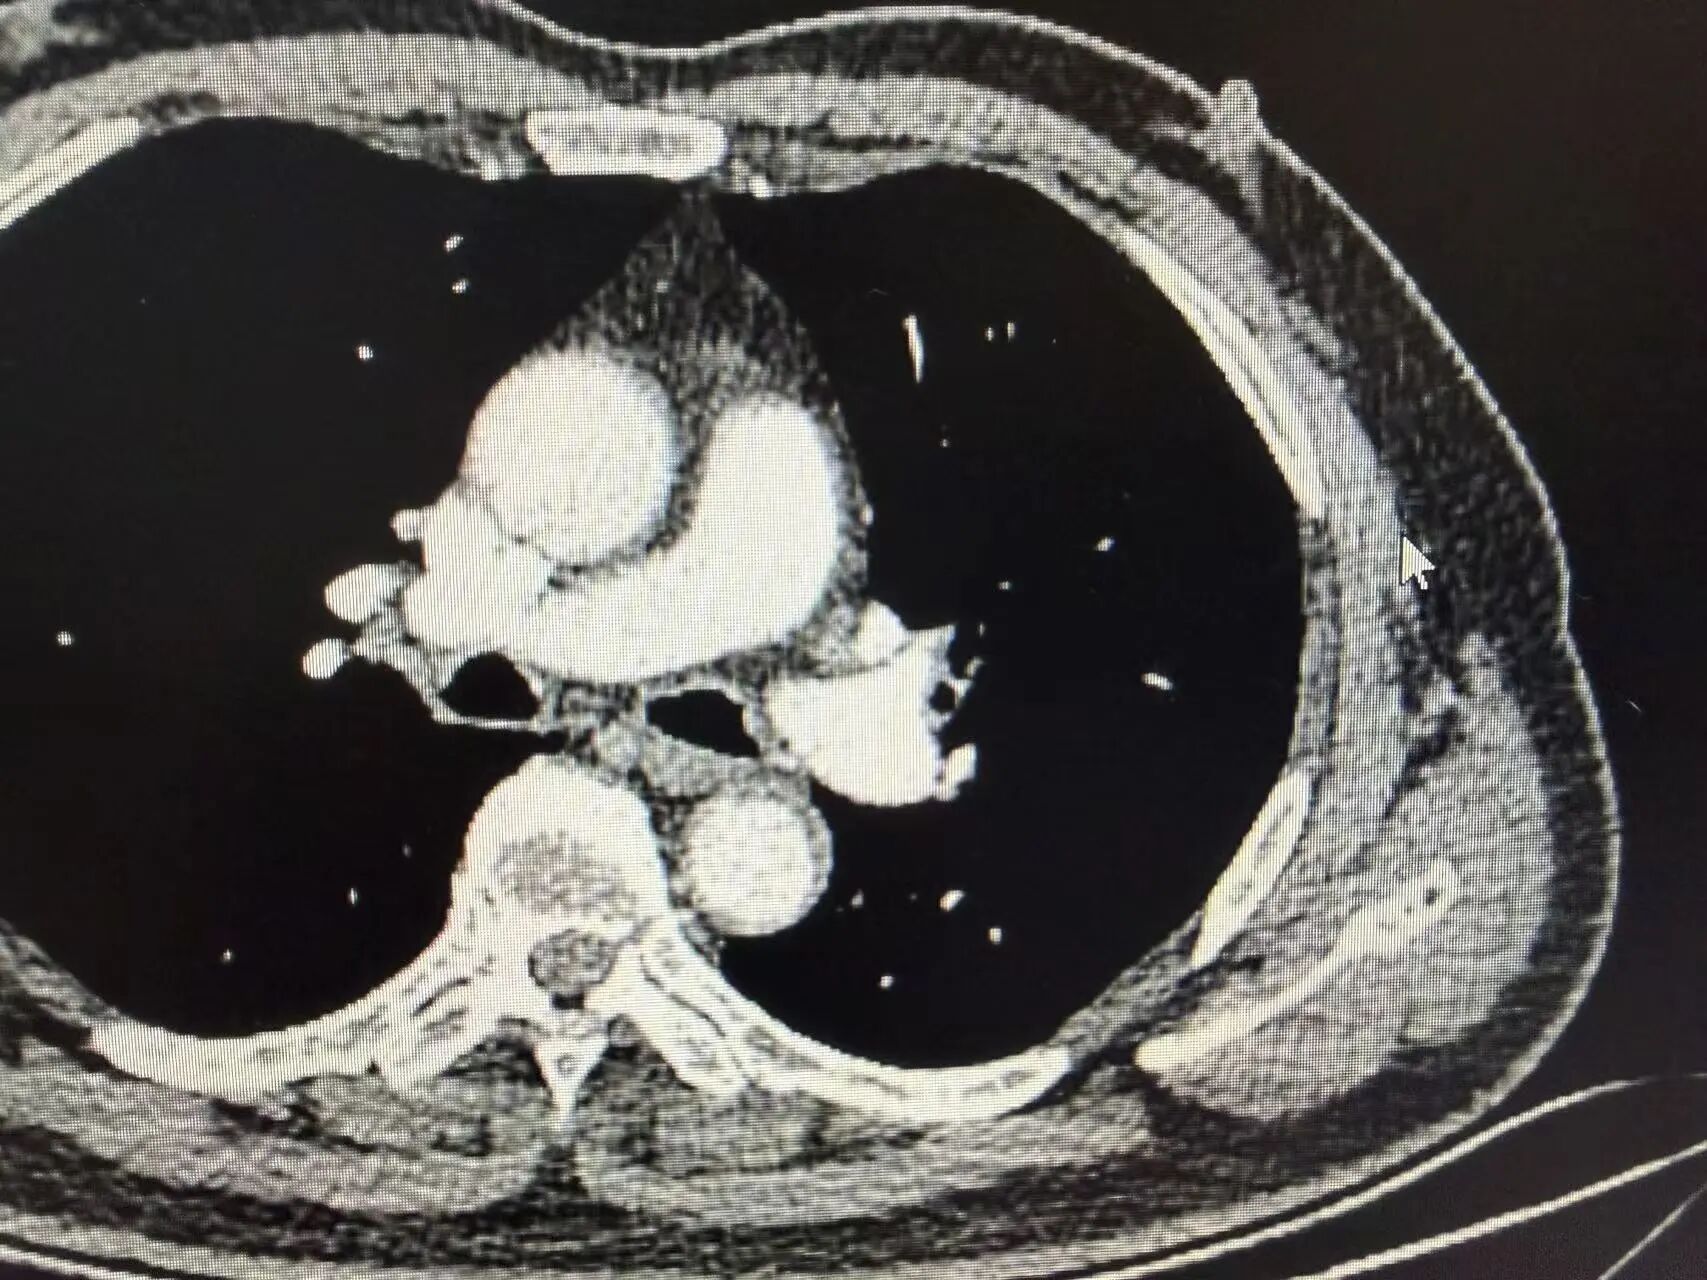

胸部增强CT结果显示:左上肺可见明显占位性病变,体积较大,同侧肺门淋巴结伴随肿大。后续穿刺病理活检明确诊断为肺鳞状细胞癌,结合淋巴结转移情况,分期为局部晚期(Ⅲa期)

新辅助治疗前CT影像